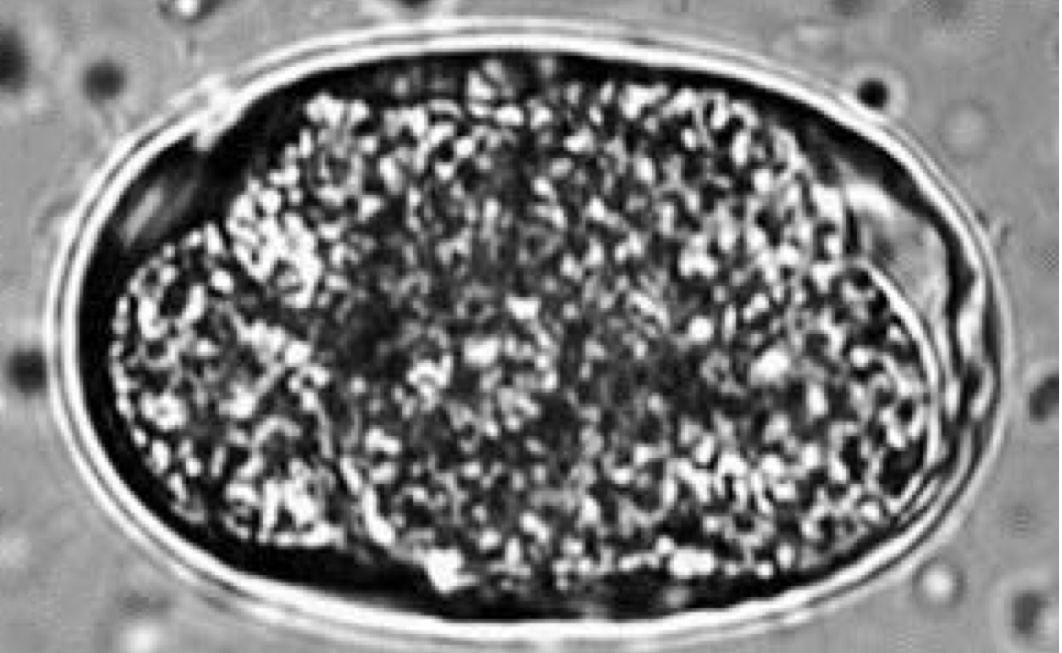

Characteristics of Strongyloidea (Ancylostoma) species

PPP - depends of species and route of transmission

route of transmission: ingestion of eggs, transdermal, across placenta/mammary milk

Dx: fecal flotation

attach to small intestine of cats, dogs and large animals

produce severe anemia in kittens and puppies

ZOONOTIC

eggs:

oval or ellipsoid, thin walls with 8-16 cells

larvate rapidly in environment (fresh feces needed)

prevention: interceptor, heartguard

treatment: mebendazole, fenbendazole